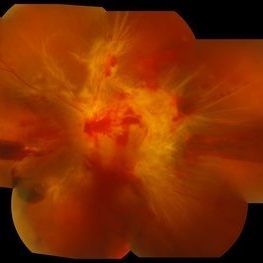

Swept Source OCT angiography (montage photography) of a 57-year-old woman with proliferative diabetic retinopathy in her both eyes.

Photographer: Nanda Lessi Hafni Eka Putri, MD (Ophthalmologist) & Ryan Mishbahuddin (Nurse), Ciawi General Hospital (Rumah Sakit Umum Daerah Ciawi)

Imaging device: DRI OCT Triton Plus

Condition/keywords: fundus photograph, montage, optical coherence tomography (OCT), swept source, wide angle imaging